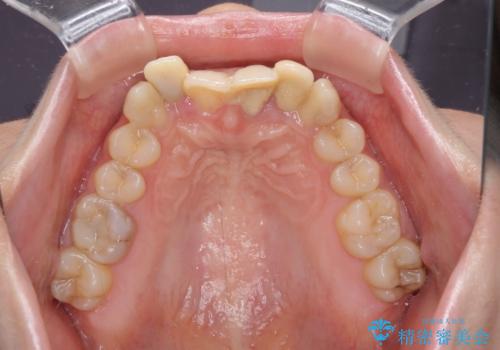

- 前歯のデコボコと、その結果むし歯が進行していることを気にして来院された患者様です。

前歯や奥歯の根管治療を行い、その後上下左右の第一小臼歯4本を抜歯してワイヤー装置にて矯正治療を行うこととしました。

矯正治療後には、根管治療を行った歯をオールセラミッククラウンにて補綴治療を行うこととしました。